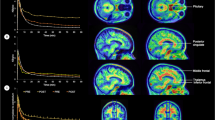

There was no significant difference in each sex steroid concentration between AD and control groups both in the cortex and white matter (Table 1). BMI in the AD group was lower than that in the control group although statistical significance was not achieved (16.1 vs. 19.3, P = 0.0752). The association between each sex steroid concentration and BMI is shown in Fig. 2. Concentrations of E1 and E2 correlated positively with BMI in both the cortex and white matter, with particularly high correlation coefficient in controls (Table 2). The correlation coefficient was lower in the AD group than in controls, with the slope among AD patients being larger for BMI ≥ 17.5 than for BMI < 17.5. Concentrations of E1 and E2 were significantly lower in subjects with BMI < 17.5 than in those with BMI ≥ 17.5 both in the cortex and white matter (Fig. 2 and Table 3). Adione concentration did not present such a clear association with BMI (Fig. 2, Table 2 and Table 3).

The Allred score16,17,18 was adopted for assessing expression of ERs, because it is an objective and easy method to semiquantatively estimate ERs in a large area of target tissue. In the white matter, glial nuclear ER-β1 staining was clearly observed for most of the controls, but this was not true for AD patients (Fig. 3c,d). The Allred score for ER-β1 in the white matter was significantly higher in controls than in AD (6.5 ± 0.3 and 3.2 ± 0.3, respectively. P < 0.0001). As for ER-α, nuclear staining was not seen in the white matter irrespective of the antibodies used (Fig. 3g,h). In the cortex, the nuclear staining was insufficient to be evaluated irrespective of the ER type or disease status (Fig. 3a,b,e,f).